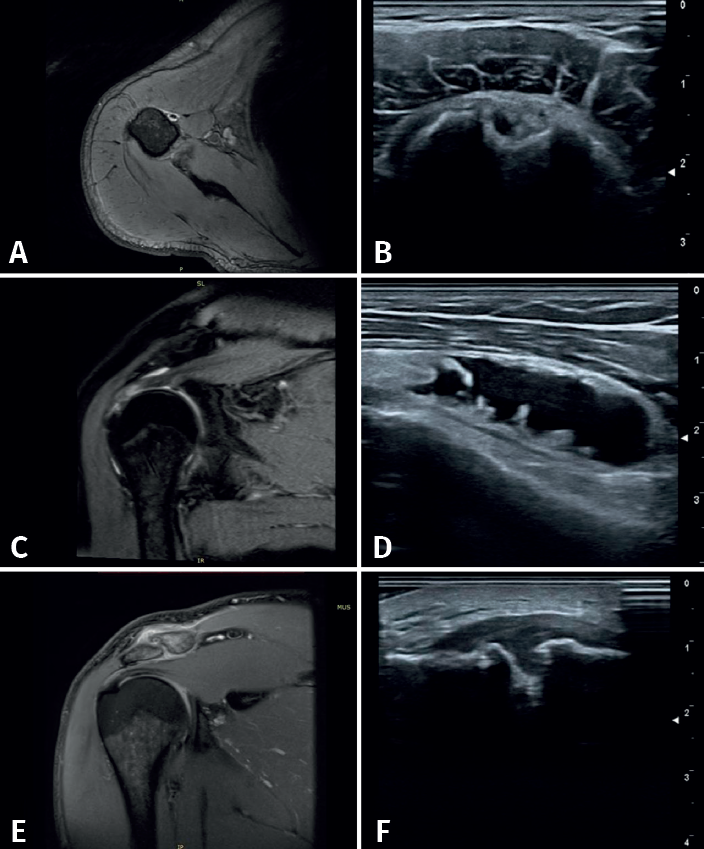

Se definieron los diagnósticos ecográficos de la siguiente manera (Figura 2): 1) tendinopatía: alteración de la ecoestructura fibrilar con alternancia de imágenes hiper- e hipoecogénicas a pesar de la corrección de la anisotropía con movimientos del transductor; 2) rotura tendinosa: imagen anecogénica intratendinosa que puede incluir a la rotura parcial (de tamaño variable con interrupción parcial de la ecoestructura normal), la rotura parcial del espesor completo (la cual abarca el espesor tendinoso en su totalidad) y la rotura completa (en la que se observa discontinuidad del tendón, generalmente presentándose adelgazado y en ocasiones con retracción tendinosa). Otras lesiones: la bursitis se observa como imagen anecogénica de más de 2 mm de grosor, localizada o generalizada entre en tendón del supraespinoso por abajo y el músculo deltoides por arriba o el borde lateral del troquíter; la artrosis acromioclavicular se caracteriza por irregularidades de sus perfiles corticales con la presencia de osteofitos y distensión de la cápsula; la rotura de labrum posterior con discontinuidad dada por una imagen hipoecoica en el borde de este; y la tendinopatía calcificante: imagen hiperecogénica sólida, única o múltiple, de tamaño variable, con o sin sombra posterior(6)(Figura 3).

En la articulación del hombro, la RM ofrece una evaluación global y más completa que la ecografía, ya que se pueden estudiar áreas que no son de acceso por este último método de imagen, refiriéndonos en particular al área intraarticular (cartílago y labrum articulares) y los tejidos blandos profundos. La RM también está indicada cuando existe la sospecha de un proceso neoplásico, particularmente si afecta la médula ósea, la cual no es de acceso por ecografía, así como en otras patologías intraarticulares como cuerpos libres en esta área o disminución con lesión del cartílago articular. Por otro lado, existen diversos escenarios en los que la ecografía tiene ventajas sobre la RM, como en la evaluación de cuerpos extraños en los tejidos blandos y lesiones que requieren una maniobra dinámica específica, como en el caso de subluxaciones tendinosas(19).